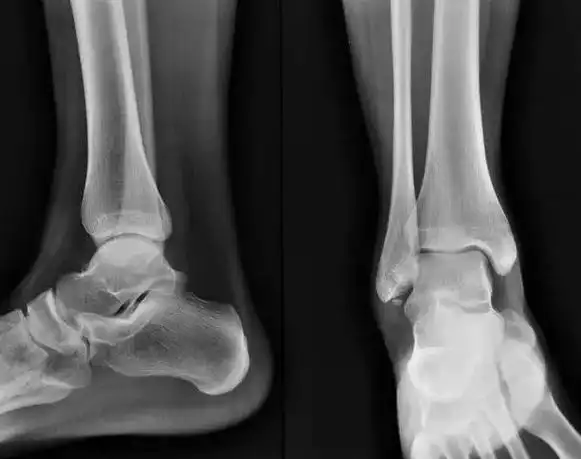

右跟骨骨折

【读片】跟骨病例. [病例帖]

患儿,男,11岁,跟骨骨骺炎,跟骨侧位片可见跟骨骨